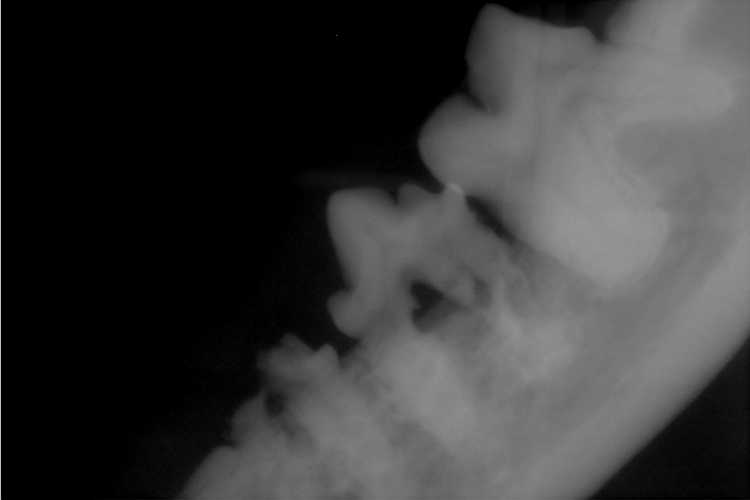

もらった写真ファイルから1枚。

奥歯を横から撮ったレントゲン写真

歯の真ん中に穴が開いているようにみえますが、

歯茎がやられて下がってしまいこんな風になっているわけです